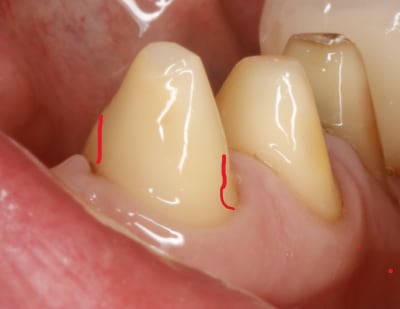

bon maintenant on va s occuper des autres .

les autres , accessoires , faut qu elles suivent le mouv s agirait pas quelles n en face qu à leurs tête . .

elles sont là pour s intégrer au bridge et si possible en augmentant la stabilisation .

ce qui veut dire qu il ne faudrait pas quelles soit plus ou moins rétentives que les canines .

il ne s agirait pas :

qu elles créent un point de rotation en étant plus rétentives

ou bien qu elles soient moins rétentives auxquelles cas elles ne serviraient à rien .

oui pcq c est le plus fort qui prime à ce jeu là donc le mieux c est tous pour un , le bridge unificateur .

et pour cause c est un bridge de contention .

deja qu elles tiennent par miracle , autant qu elles ne nous emmerdent pas , surtout si si on risque de les perdre un jour .

donc on les parallélise aux canines sur les faces vest .

traits verts sur photo